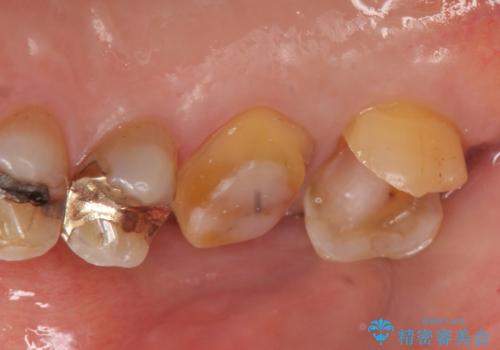

右上6,7の金歯を外したところ、虫歯が歯茎より深い位置まで進行していたため歯周外科を行いました。

その後歯茎の回復を待ち、オールセラミッククラウンおよびセラミックインレーによる補綴・修復を行いました。

虫歯が進み歯茎より深くなってしまうと、虫歯を取り残してしまうリスク、樹脂の硬化の妨げ、補綴物の不適合、歯肉炎・歯周病のリスクの増大等様々な弊害が起こり得ます。

そのため当院では歯周外科手術(歯茎を下げる手術)や歯の挺出による、虫歯が歯茎より深いという問題の解決を推奨しております。